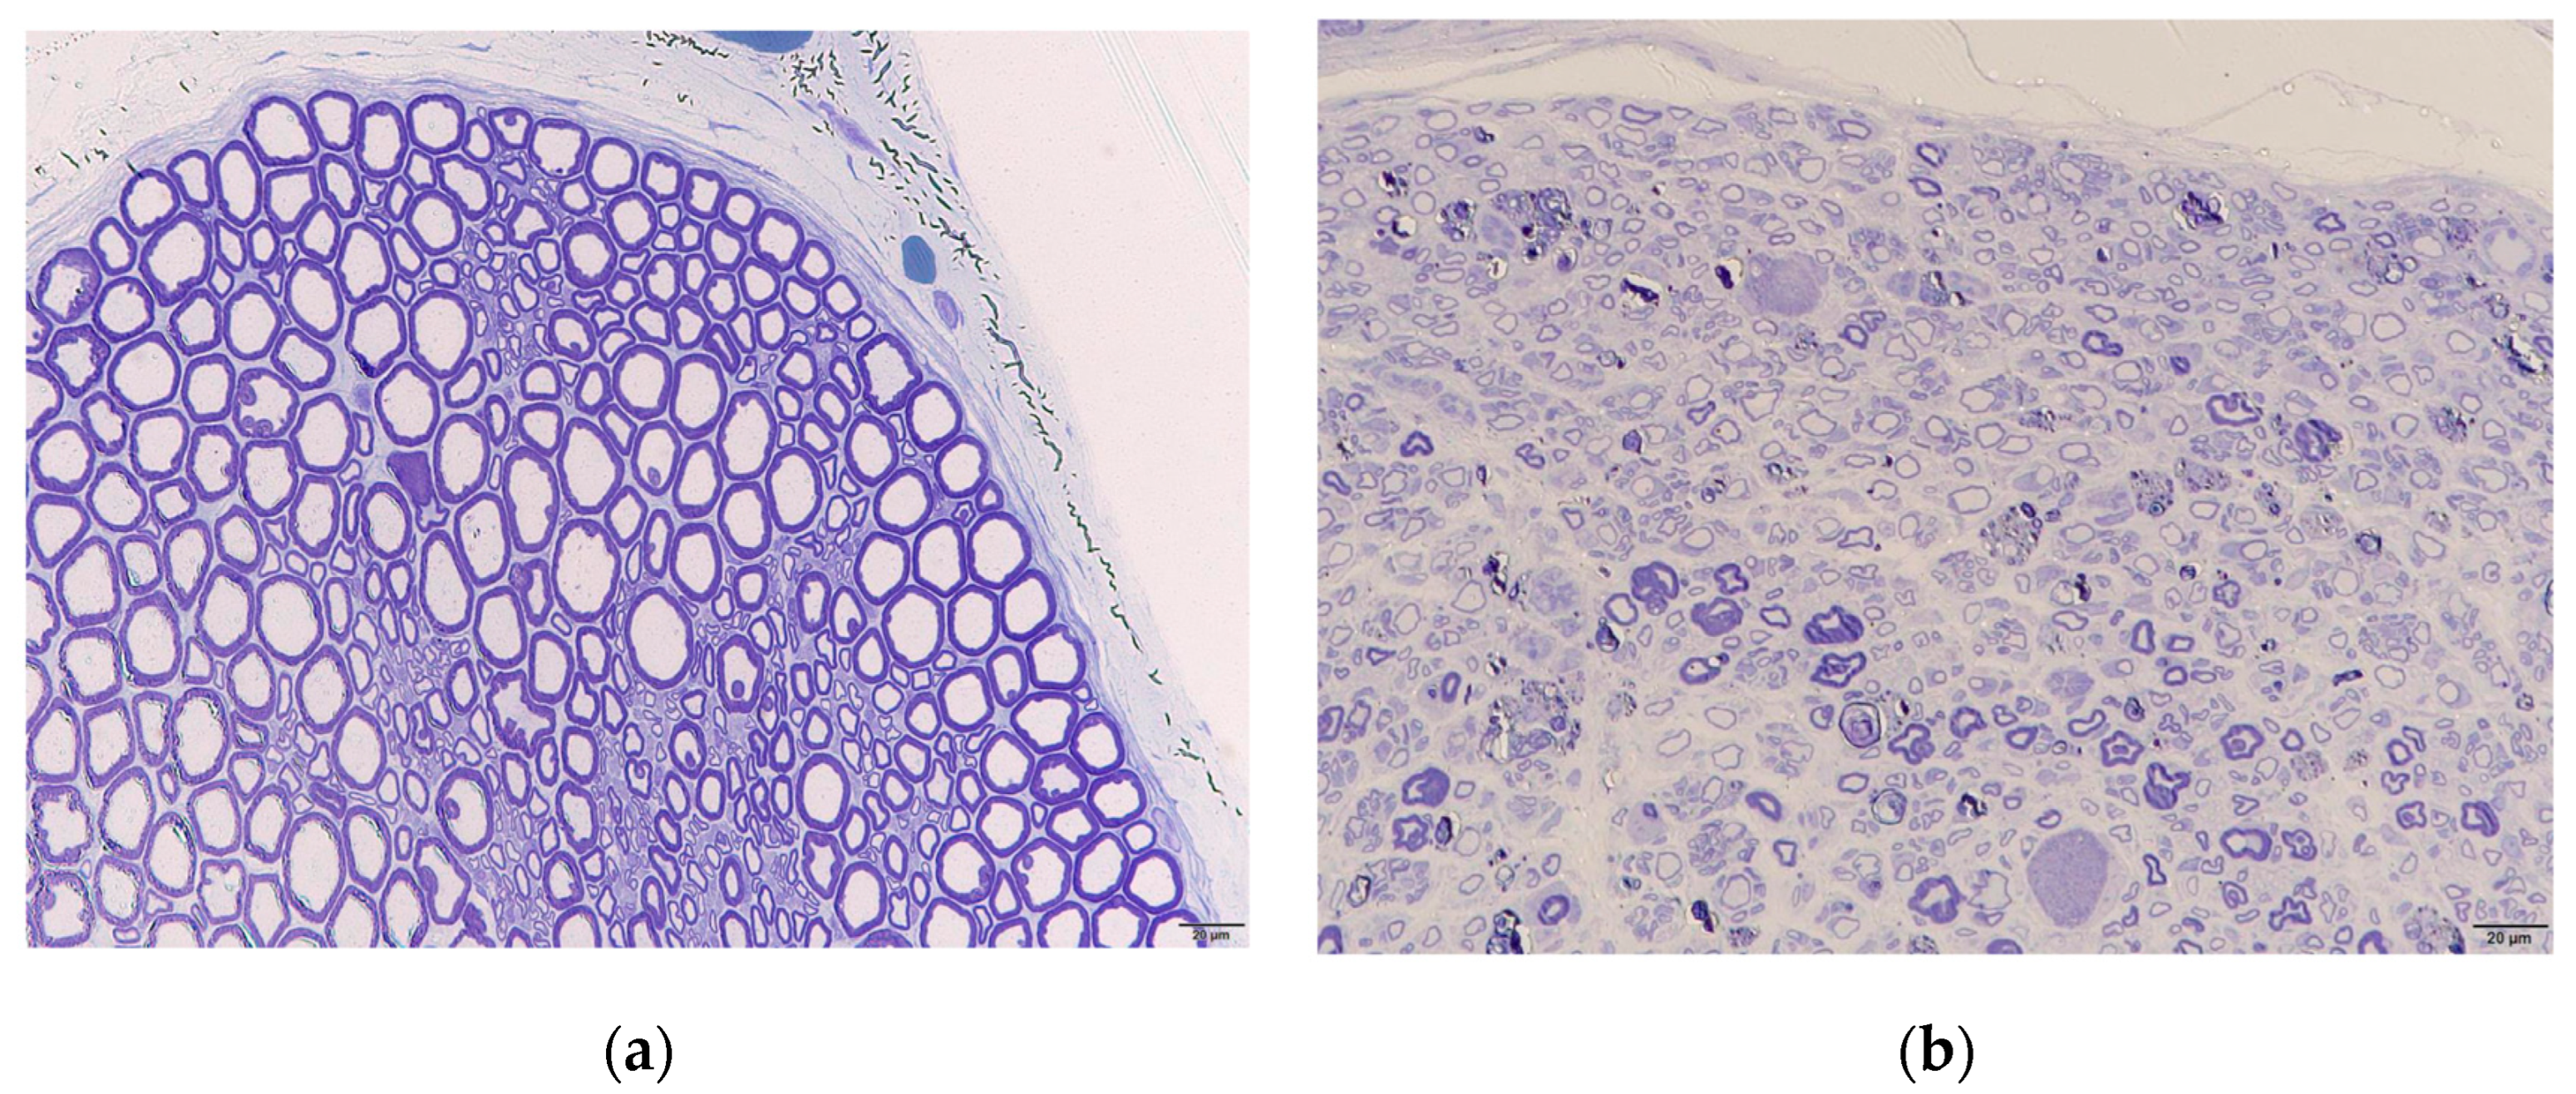

3.3. Histological Examination